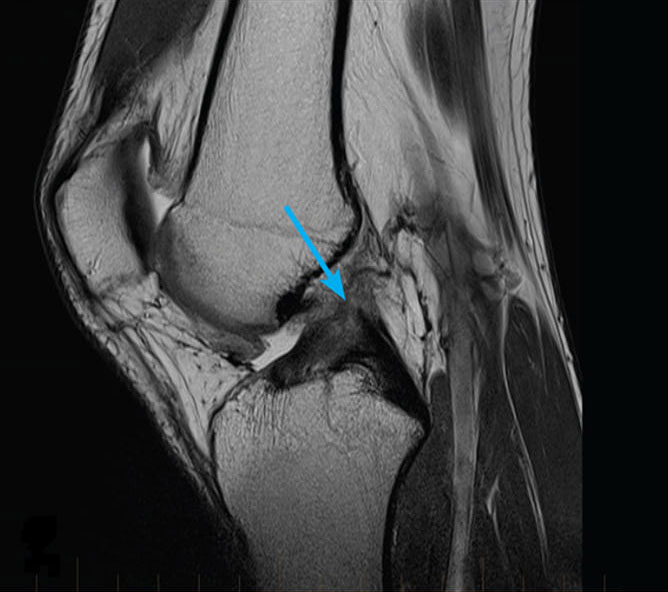

Uitați-vă la aceste imagini, puteți vedea că în imaginea din dreapta nu există spațiu articular, oasele se freacă unele de altele, provocând dureri puternice. Iar acest proces este foarte greu de oprit! În câțiva ani, persoana va deveni invalidă și nu va mai fi capabilă să aibă grijă de sine.